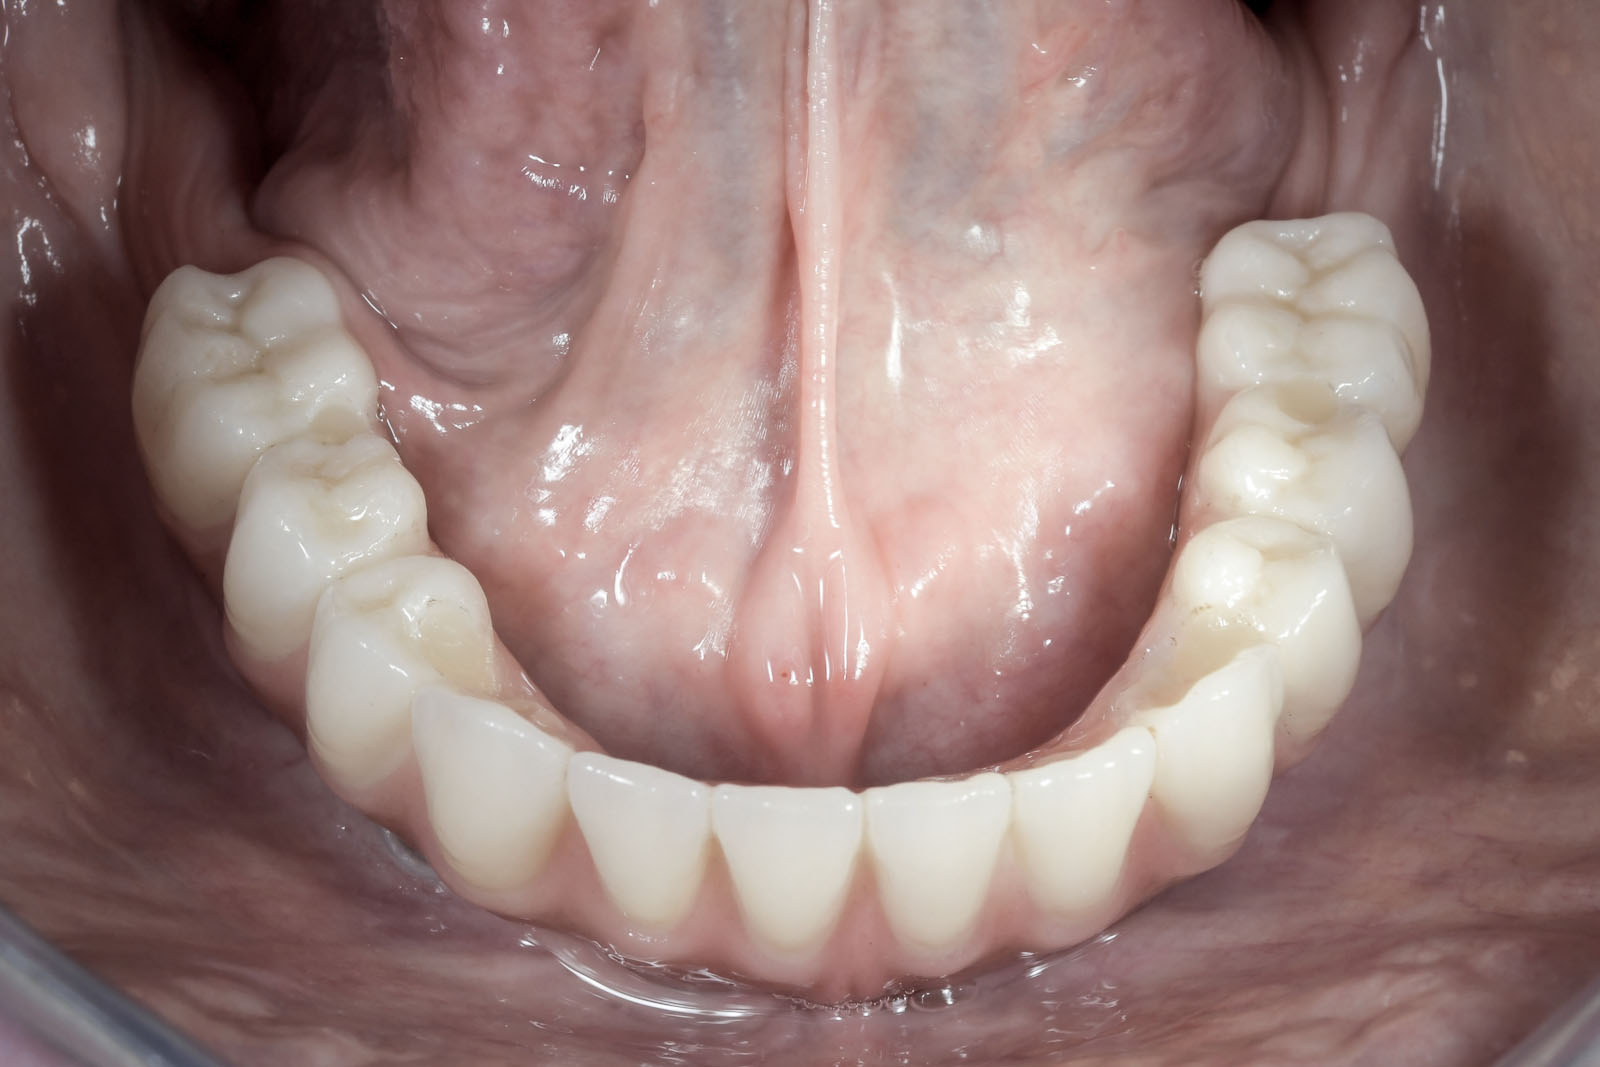

ROZWIĄZANIA PROTETYCZNE ALL-ON-4

Na implantach wszczepionych zgodnie z protokołem all-on-4 możliwe są do wykonania stabilne mosty, jak również ruchome protezy typu nakładowego. Uproszczenie i optymalizacja rozwiązań protetycznych możliwa jest dzięki zastosowaniu kątowych łączników typu MultiUnit (17°, 30°), które po przykręceniu do pochylonych implantów umożliwiają łatwe mocowanie mostu i obsługę serwisową pacjenta.